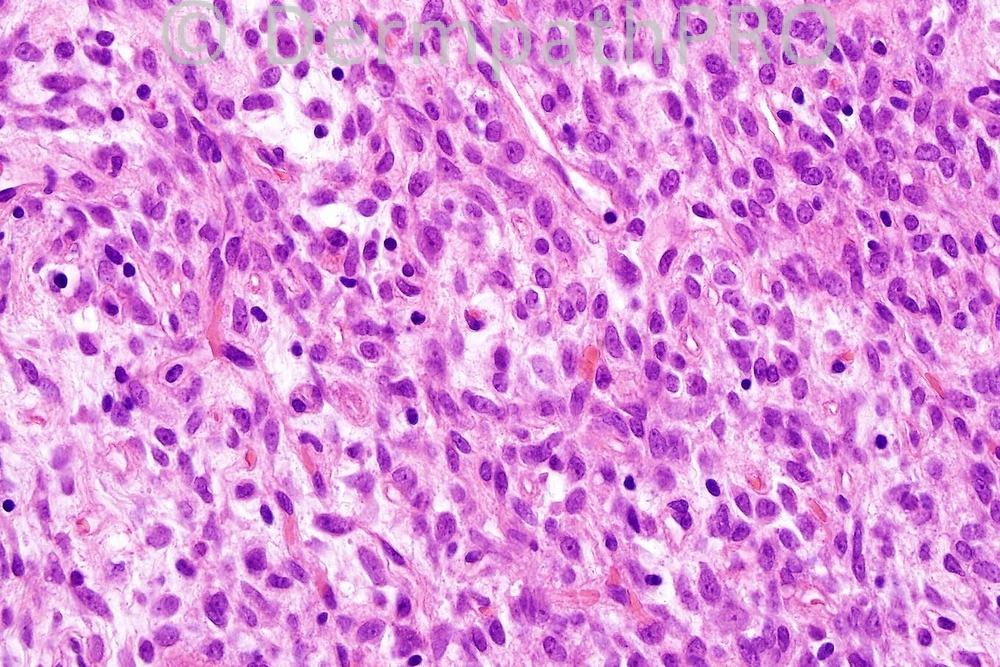

Male 56 years, nodule on arm.

Those of you who diagnosed solitary fibrous tumor can go to the top of the class!!! This was a very difficult case. The tumor is typified by a random spindled cell bland infiltrate devoid of any real pattern. A storiform growth pattern for example would be very much against the diagnosis. In the top two figures, cellular and hypocellular foci are shown. This is a typical feature. The hyalinization often having a star-like appearance is a very useful clue to the diagnosis. Many examples have a hemangiopericytomatous vasculature which wasn't really evident in this case. the tumor cells showed very strong CD34 expression.

There are vessels surrounded by "hyaline" surrounded, in turn, by monomorphic, small oval cells. I would bet on a solitary fibrous tumour. Is CD34 positive?